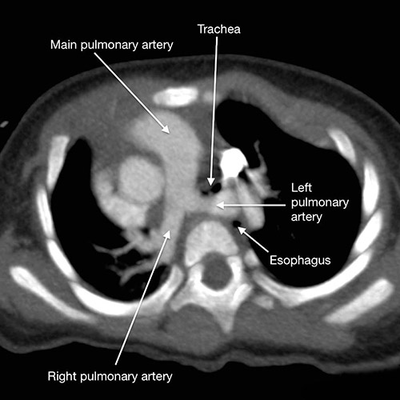

肺动脉吊带是一种罕见的先天性心血管畸形,又名迷走左肺动脉,是左肺动脉异常起源于右肺动脉的后方,呈半环形跨过右主支气管向左穿行于食道前和气管后到达左肺门,常合并气管下段、右主支气管和食管不同程度的压迫。此外,动脉导管或韧带向左后方与降主动脉相连,此结构和异常的左肺动脉一起形成的血管环可压迫左主支气管。

肺动脉吊带是一种罕见的先天性心血管畸形,又名迷走左肺动脉,是左肺动脉异常起源于右肺动脉的后方,呈半环形跨过右主支气管向左穿行于食道前和气管后到达左肺门,常合并气管下段、右主支气管和食管不同程度的压迫。